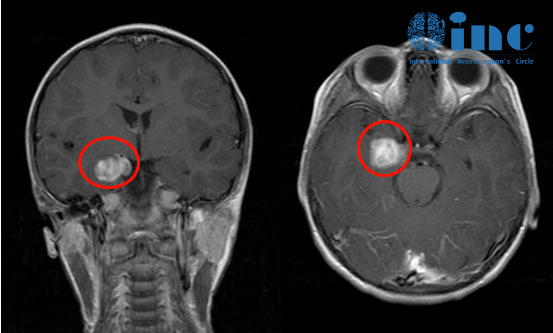

術(shù)前影像

手術(shù)七年后復(fù)發(fā)影像

在手術(shù)切除后,Jimmy享受了七年的寧靜時光,但在他14歲那年癲癇再次發(fā)作,檢查發(fā)現(xiàn)他的內(nèi)側(cè)顳葉腫瘤出現(xiàn)了小的殘留病變,周圍可能也是致癇灶,這些導(dǎo)致了癲癇復(fù)發(fā),如不及時治療,可能會逐漸回到術(shù)前狀態(tài),再次陷入癲癇的“夢魘”,但Jimmy這次不愿再次接受開顱手術(shù),他希望能盡快完成治療重返校園。